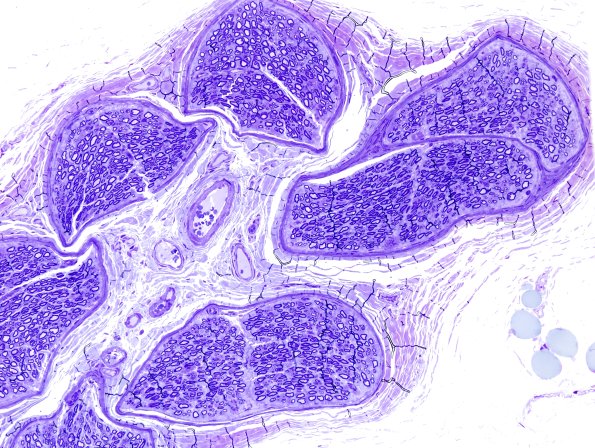

Washington University Experience | PERIPHERAL NEUROPATHY | 0 PNS ARTIFACTS | 12C2 Artifact, crush compare with adjacent block same nerve Plastic 20X 1.jpg

Two adjacent blocks of nerve with the first cut made before complete fixation and the second after fixation. (Toluidine blue stained one micron thick plastic embedded sections)